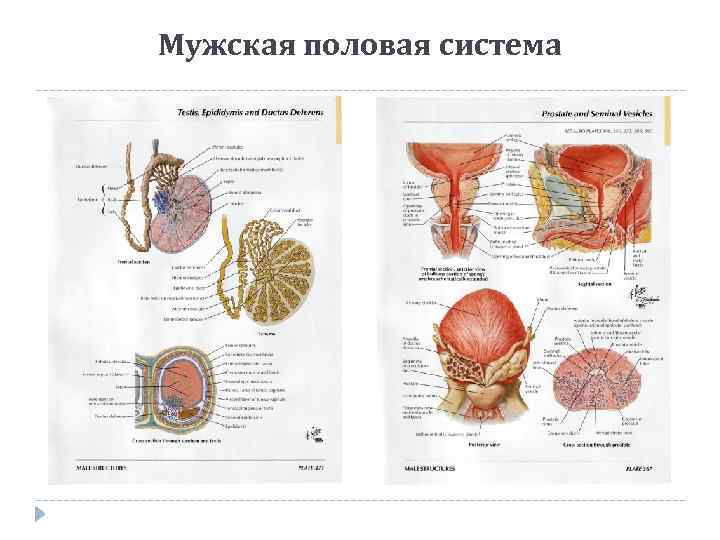

Мужская половая система

Мужская половая система

Мочевой пузырь и мужской мочеиспускательный канал

Мочевой пузырь и мужской мочеиспускательный канал

Семенные пузырьки и предстательная железа

Семенные пузырьки и предстательная железа